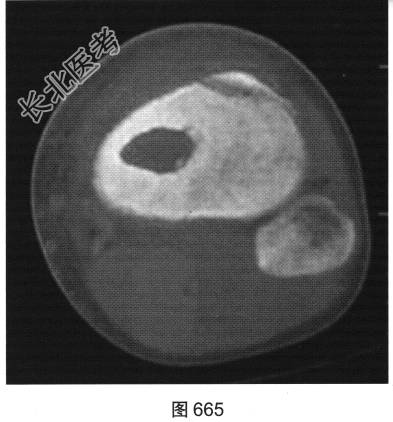

- 多项选择题3.[提示]患者行右小腿X线平片及CT、MRI检查,见图664~图666。该病最可能的诊断是( )

A、Brodie骨脓肿

- 多项选择题4.Brodie骨脓肿的诊断依据是( )

A、MRI囊内为液性信号并见环状等信号薄壁,周围见水肿区

B、CT示囊样骨质破坏,边缘有硬化

C、患者为青少年

D、X线见类圆形骨质破坏,边界清楚伴边缘骨质硬化

E、发热、患肢疼痛、肿胀等典型症状

F、起病较急